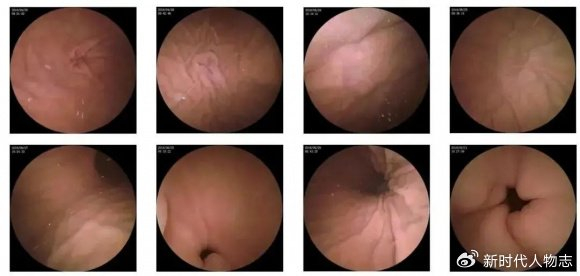

肛門息肉早期圖片展示

(請(qǐng)?jiān)诖颂幉迦敫亻T息肉早期圖片)

圖片展示可以幫助公眾更直觀地了解肛門息肉的外觀和癥狀,請(qǐng)注意,由于個(gè)體差異和拍攝角度等因素,圖片僅供參考,不能作為診斷依據(jù)。